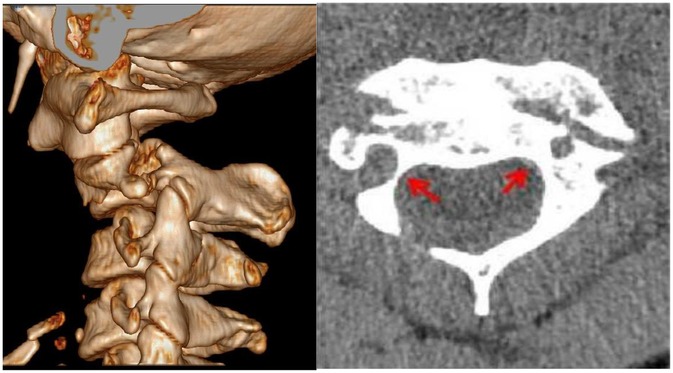

Objective: This retrospective study aimed to analyze the accuracy and safety of pedicle screw placement in upper cervical spine surgery for Hangman's fractures, particularly in cases with high-riding vertebral artery (HRVA) at C2, using navigation technology and 3D-printed patient-specific templates. Methods: We included 33 patients with Hangman's fractures who underwent posterior cervical fixation with bone graft fusion or non-bone graft fusion surgery between January 2013 and January 2023. Patients were divided into two groups based on the intraoperative pedicle screw placement method: Group A (n=15) utilized a navigation system, and Group B (n=18) used a 3D printed navigation template. Clinical and radiological data were collected and compared. Results: One hundred and forty-four screws (66 navigated, 78 3D-printed templates) were inserted without vertebral artery, spinal cord, or nerve injury. Operative time per screw: Group A 24.0±5.6 min vs Group B 18.7±4.1 min; mean difference 5.3 min (22% reduction; 95% CI -9.1 to -1.5; P=0.018). Intra-operative blood loss:152±29 mL vs 105±19 mL; mean difference 47 mL (95% CI -66 to -19; P=0.001). Overall accuracy (Grade 0+1) was 98.5% (65/66) vs 98.7% (77/78) (odds ratio 1.05; 95% CI 0.11-10.2; P=0.97). In the Type-III fracture subgroup (8 screws per group), templates achieved 100% accuracy vs 87.5% with navigation (P=0.032) and lower cortical penetration (12.5% vs 37.5%; P=0.008). Post-operative VAS and NDI improved comparably (all inter-group P>0.05). At 24-month follow-up, all fractures had healed; C2/3 fusion rates did not differ (facet fusion 100% vs 100%; inter-body fusion 39% vs 39%; P>0.99). Conclusion: The use of 3D-printed patient-specific templates in upper cervical spine surgery for Hangman's fractures, especially in the presence of HRVA, is effective and safe. It offers comparable accuracy to navigation-assisted surgery while reducing operative time and blood loss. This approach may be particularly beneficial in minimizing the risk of vertebral artery injury and optimizing surgical outcomes. Compared to navigation technology, it can effectively improve the accuracy of screw placement in extremely unstable fractures.